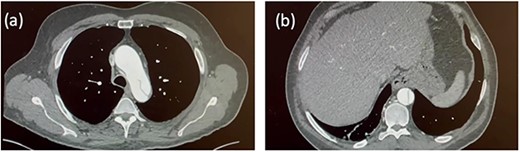

Four months later, the patient developed dyspnoea and orthopnoea. He was also found to be positive for COVID-19. He was clinically well and his hepatitis C viral load was undetectable. A CT aorta-thorax demonstrated that the ascending aorta had further dilated (60 × 61 mm). This aneurysm compressed the trachea resulting in his acute respiratory symptoms (Fig. 3). The patient was diagnosed with an acute-on-chronic type A aortic dissection with mild–moderate aortic regurgitation. Emergency thoracic aortic surgery was performed with remodelling of the sinotubular junction with a prosthetic graft and aortic valve repair. The patient had a long post-operative recovery phase complicated primarily due to his COVID-19 diagnosis. He was discharged 43 days after his surgery.

CT aorta thorax on patient’s re-admission four months later. Ascending aortic aneurysm has increased in size (measuring 60 × 61 mm) compressing the trachea.